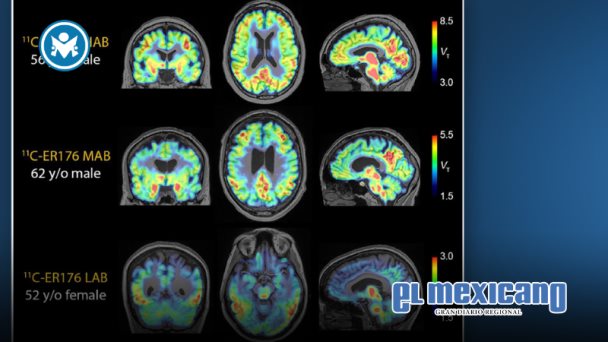

La especificidad anatómica de los marcadores de inflamación en los estudios PET (por sus siglas en inglés) es crucial, ya que las enfermedades que causan demencia afectan distintas regiones del cerebro.

El liderazgo del Hospital Houston Methodist en esta área queda de manifiesto en el desarrollo innovador de tecnología de imagen PET, en particular con el uso del nuevo trazador PET 11C-ER176.

A diferencia de otros trazadores PET, el 11C-ER176 permite observar la inflamación de forma eficaz en todos los tipos genéticos de pacientes.

Este trazador actúa sobre la proteína TSPO, un marcador de inflamación, lo que permite a los científicos obtener imágenes detalladas incluso en personas que antes no podían ser evaluadas debido a su perfil genético.

Gracias a este equipo, los investigadores pueden diferenciar con claridad qué estructuras del cerebro están afectadas por inflamación y cuáles contienen proteínas anormales. Esta distinción no podía hacerse en estudios anteriores, incluso en algunos considerados fundamentales, debido a la menor resolución de las imágenes.